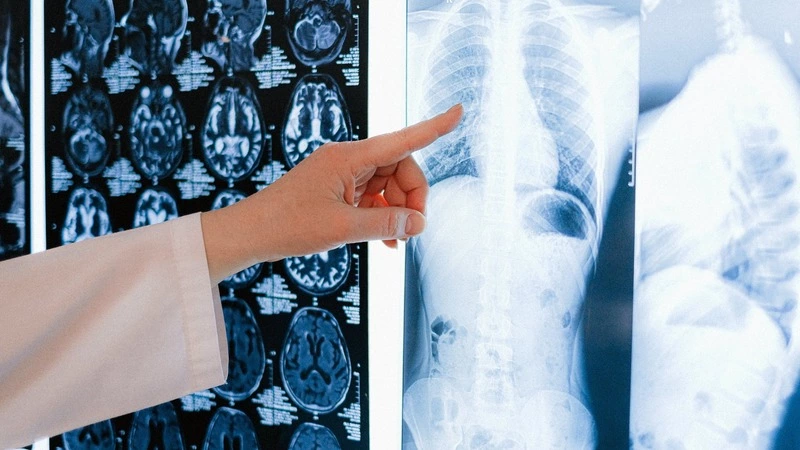

Компания СберМедИИ усовершенствовала сервис «КТ Лёгких». Теперь искусственный интеллект научился выявлять онкологические заболевания на ранней стадии при анализе КТ грудной клетки и может помогать врачам при диагностике.

Рак лёгких на ранних этапах выглядит как небольшое изменение тканей в несколько миллиметров. Теперь алгоритм способен находить минимальные узелковые новообразования в лёгких, а также подсвечивать потенциально опасные участки. Например, если размер хотя бы одного из обнаруженных новообразований превышает пороговое значение в четыре миллиметра, то сервис выделяет все обнаруженные узелковые новообразования вне зависимости от их размера, тем самым обозначая врачу участки, на который необходимо обратить внимание при анализе и принятии решения о дальнейших действиях по определению характера новообразований.

Рак лёгких — наиболее распространённое злокачественное образование в мире, а также наиболее частая причина летальных исходов среди онкологических патологий. Согласно Национальной стратегии развития искусственного интеллекта на период до 2030 года, одним из приоритетов для поддержки сферы здравоохранения является ускоренное внедрение цифровых технологий. Применение обновлённого сервиса «КТ Лёгких» может помочь врачам при выявлении новообразований на КТ снимках, способствовать повышению качества диагностики онкологических заболеваний на ранних стадиях.

Сервис «КТ Лёгких» в настоящее время используется в 30 клиниках в 19 регионах России для диагностики вирусной пневмонии в том числе COVID-19. Искусственный интеллект отмечает места и указывает процент поражённых тканей, помогая врачам в борьбе с коронавирусной инфекцией. Он является частью системного решения компании СберМедИИ — медицинского цифрового диагностического центра (MDDC), объединяющего в себе более 50 продуктов и решений СберМедИИ, а также других компаний экосистемы Сбера и партнёров.